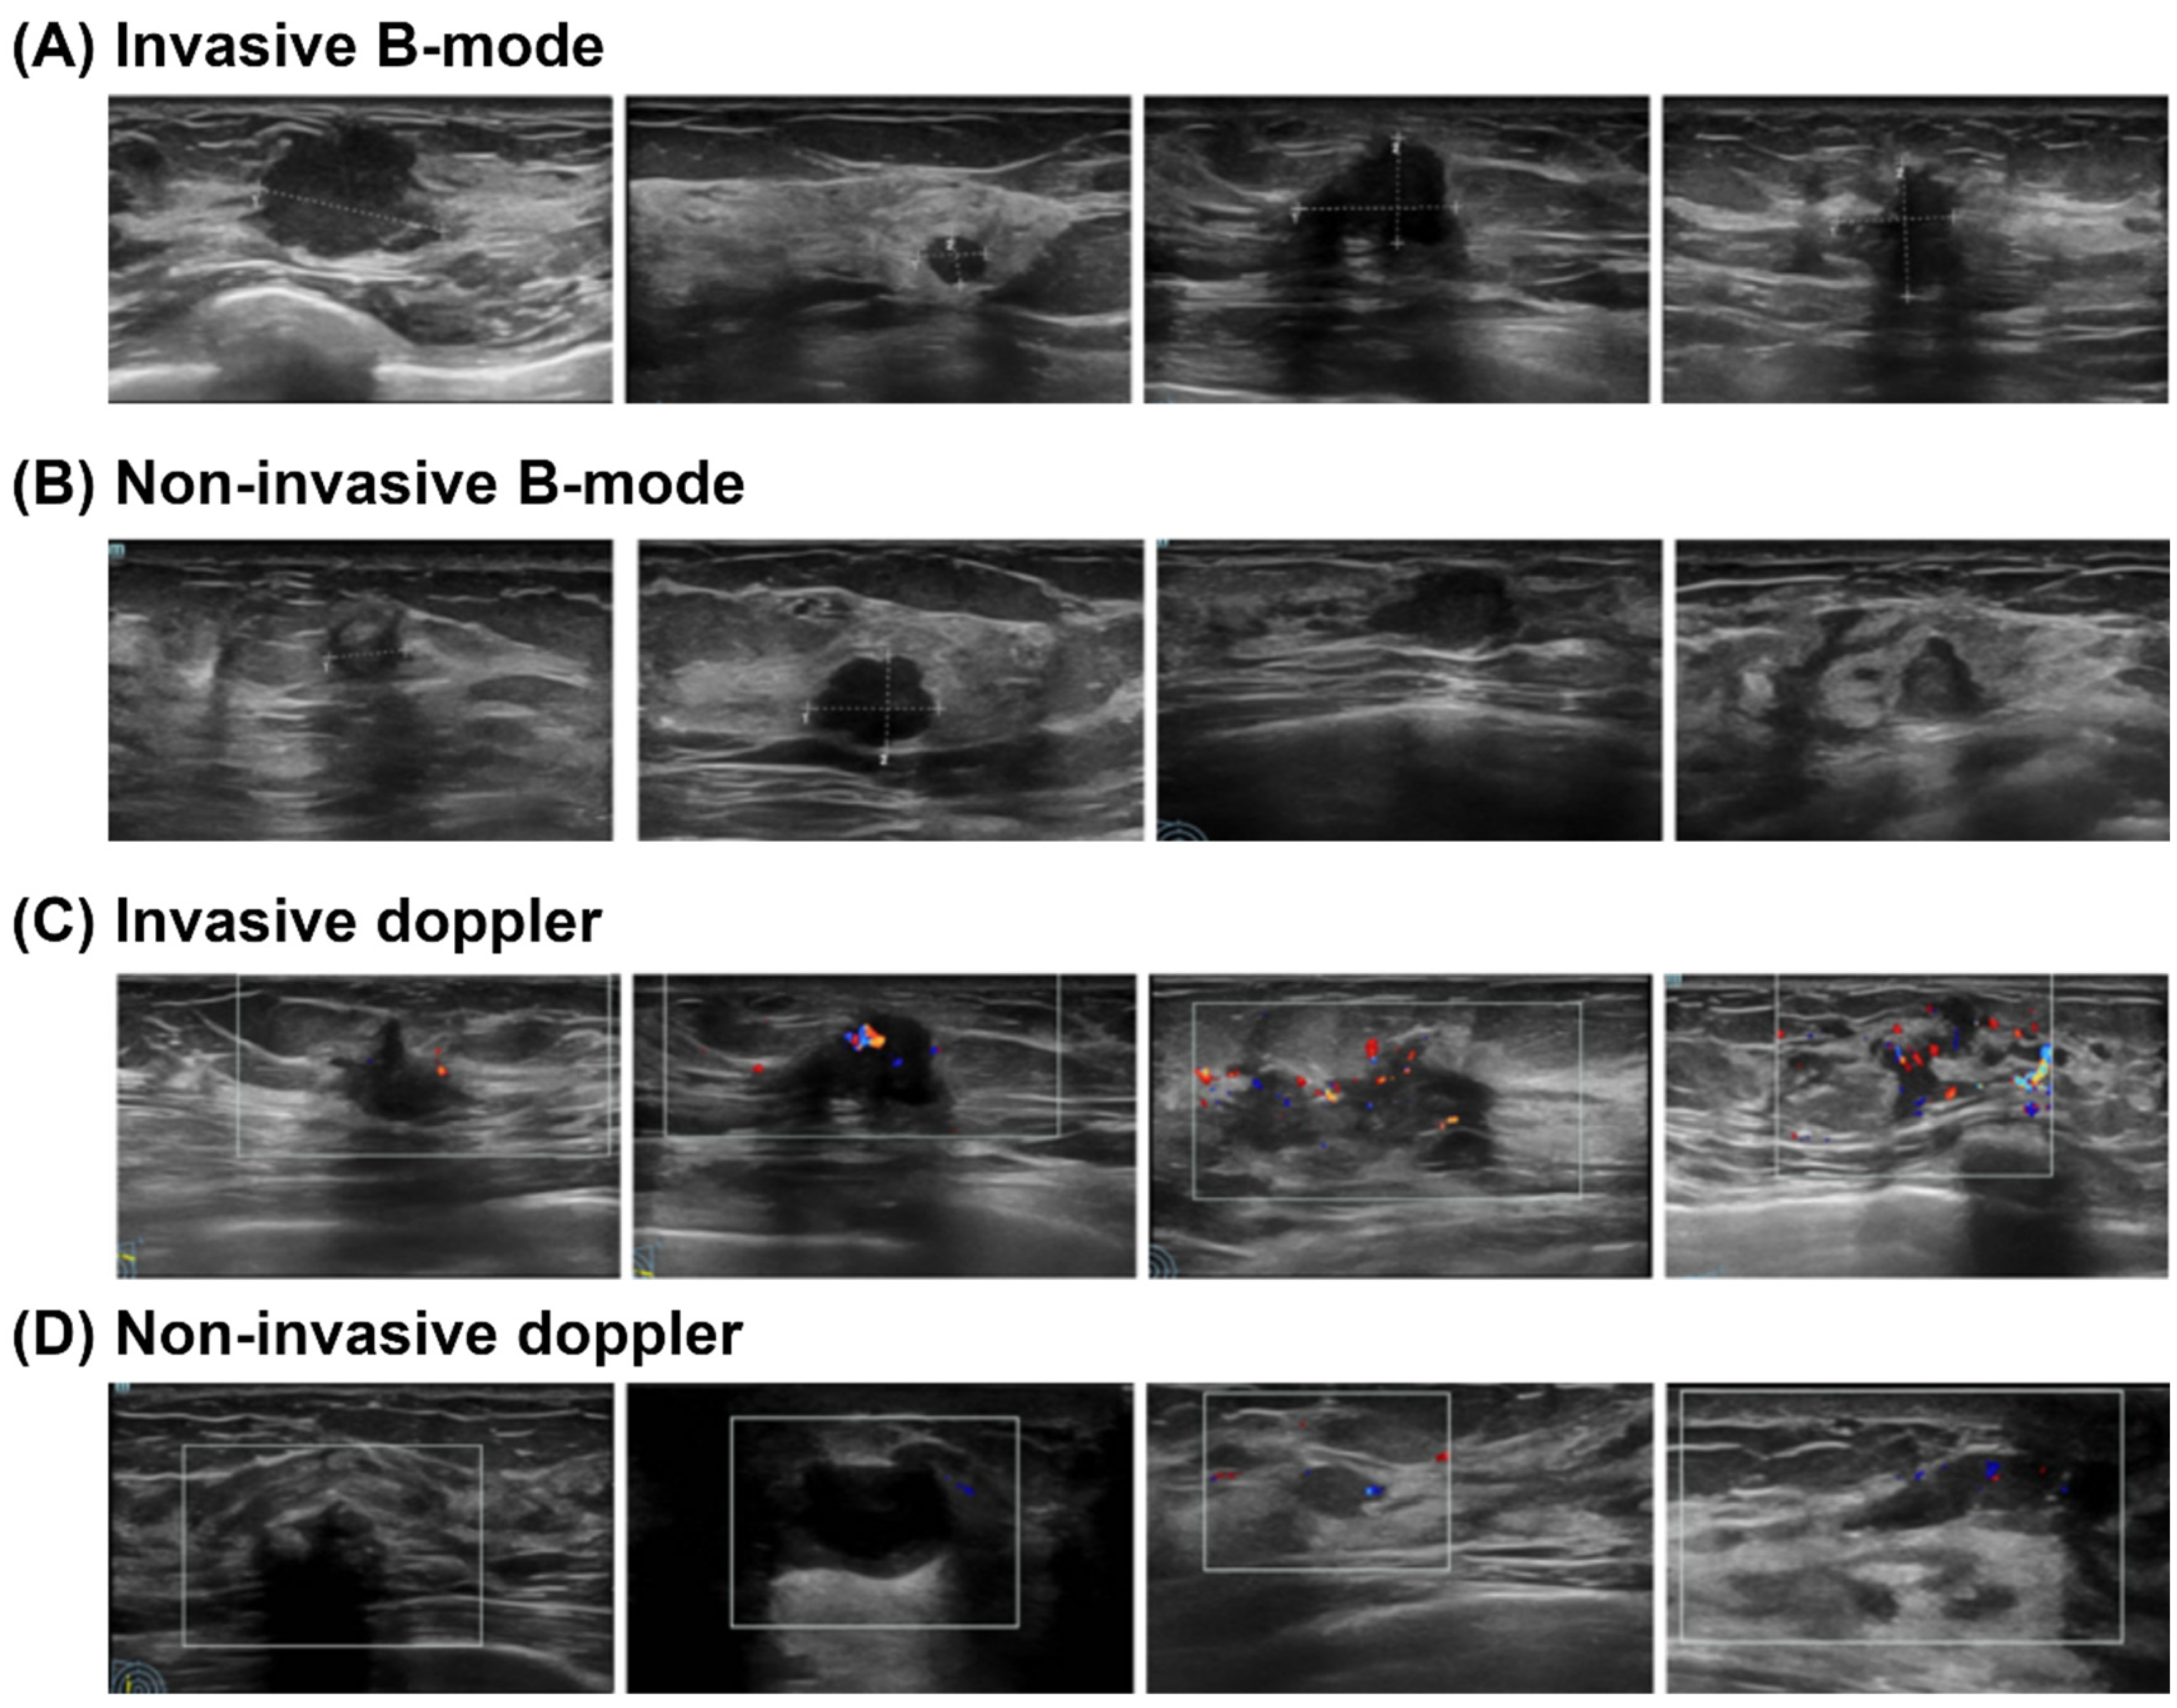

- Imaging Model: Deep learning models (including EfficientNet, ResNet101, and ViT) were developed and validated exclusively on Cohort A, utilizing the B-mode and Doppler ultrasound images. A weighted loss function was employed during training to mitigate the effects of class imbalance. This approach assigned higher penalties for misclassifying minority (invasive) class samples, thereby compelling the models to pay closer attention to these critical, less frequent instances.